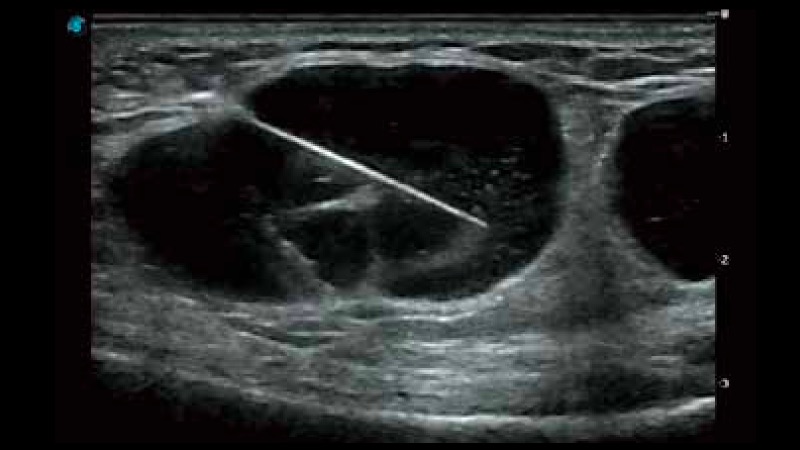

開(kāi)立醫(yī)療通過(guò)不斷的技術(shù)創(chuàng)新,為大眾的生命健康提供持續(xù)關(guān)愛(ài)。P12 Plus采用全新一代超聲成像平臺(tái),新平臺(tái)旨在將真實(shí)還原組織解剖結(jié)構(gòu)作為首要目標(biāo)。平臺(tái)采用全新集成化硬件模塊,搭載新一代芯片,系統(tǒng)性能得到大幅提升,為您的診斷提供了豐富的臨床信息。優(yōu)異的圖像表現(xiàn),豐富的探頭配置,全面的應(yīng)用功能,為您日常診斷提供了可靠的助手。

彩色多普勒超聲診斷系統(tǒng)